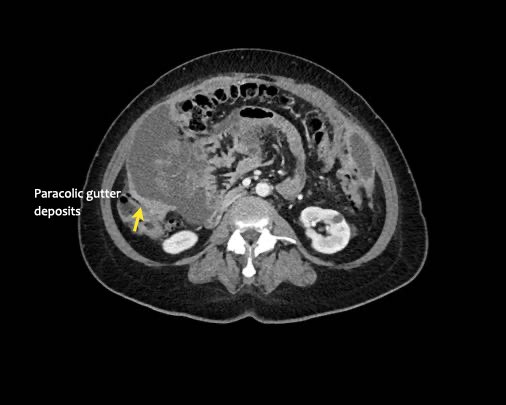

Rãnh cạnh đại tràng

Bất kỳ vị trí nào trong ổ bụng được phủ bởi phúc mạc đều có thể là đích đến của các nốt cấy ghép phúc mạc.

Các vị trí điển hình khác bao gồm rãnh cạnh đại tràng, túi cùng trực tràng-bàng quang hoặc trực tràng-tử cung, dây chằng liềm và mặt bụng của cơ hoành.